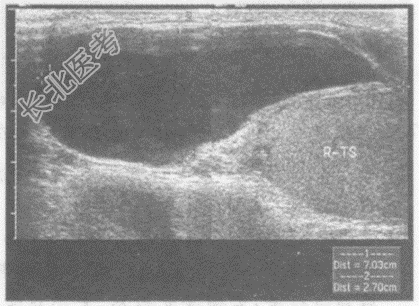

- 单项选择题临床资料:男, 63岁,自述右侧阴囊肿胀不适月余。

超声综合描述: 右侧睾丸形态、大小正常,内回声均匀。右睾丸头侧可见无回声区, 内透声欠清亮,与腹腔不相通。

超声提示:  A、右睾丸鞘膜积液

B、交通性鞘膜积液

C、右精索鞘膜积液

D、睾丸精索鞘膜积液

E、阴囊鞘膜积液